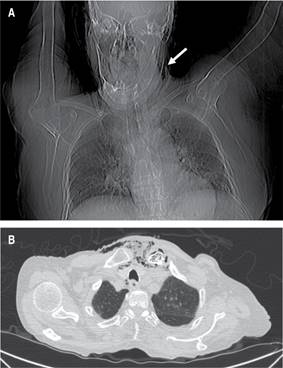

Durante el abordaje inicial en el servicio de urgencias, se decidió la colocación de sonda urinaria (la paciente aún tenía diuresis espontánea), con evidencia de piuria; se intentó colocar un acceso venoso central, palpando la presencia de enfisema subcutáneo, por lo que se solicitó realizar una tomografía computarizada; con reporte de un proceso inflamatorio localizado en la región cervical con extensión al mediastino superior, así como presencia de gas intramedular en clavícula izquierda y manubrio esternal, sugestivo de osteomielitis (Figuras 1 y 2). El estudio del líquido peritoneal obtenido a través del catéter de diálisis se encontró dentro de parámetros de referencia, por lo que ante la evidencia de choque séptico asociado a evidencia radiológica de mediastinitis Endo IIA, se propuso tratamiento quirúrgico urgente consistente en exploración y drenaje cervical, el cual no fue aceptado por los familiares de la paciente hasta 12 horas después del ingreso hospitalario. Se inició tratamiento antibiótico de amplio espectro (carbapenémico) desde el ingreso hospitalario y durante la cirugía se realizó un abordaje cervical en collar, 1 cm por encima de la escotadura esternal, se disecó por planos y se identificó presencia de líquido purulento proveniente de la articulación esternoclavicular izquierda; debido a la inestabilidad hemodinámica de la paciente, manifestada por hipotensión persistente, uso de aminas presoras con dosis progresivas y presencia de extrasístoles ventriculares, se decidió limitar la cirugía a control temporal del foco infeccioso con drenaje, irrigación y debridación parcial del área afectada.

Figura 1: A) Topograma que muestra presencia de aire en región cervical izquierda (flecha blanca). B) Tomografía computarizada en la que se observa ventana pulmonar con evidencia de aire retrotraqueal y enfisema subcutáneo.